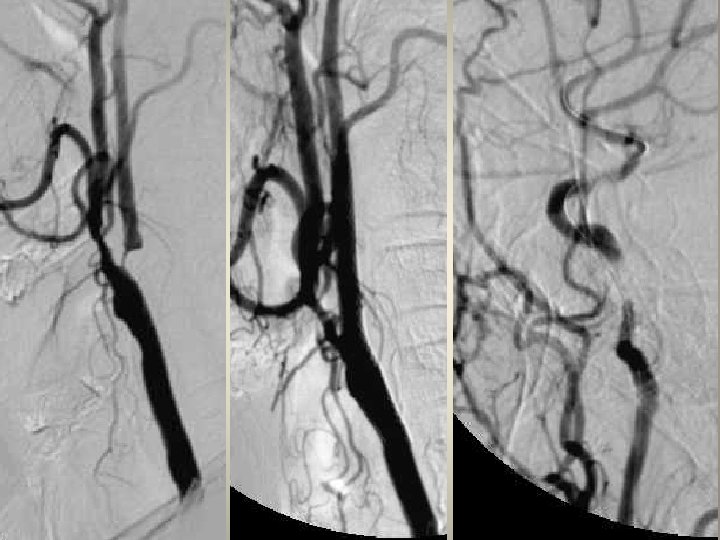

Neden stent? TANDEM lezyon

Neden stent? Distal emboli koruma

Neden stent? Eş zmanlı komplikasyon idaresi